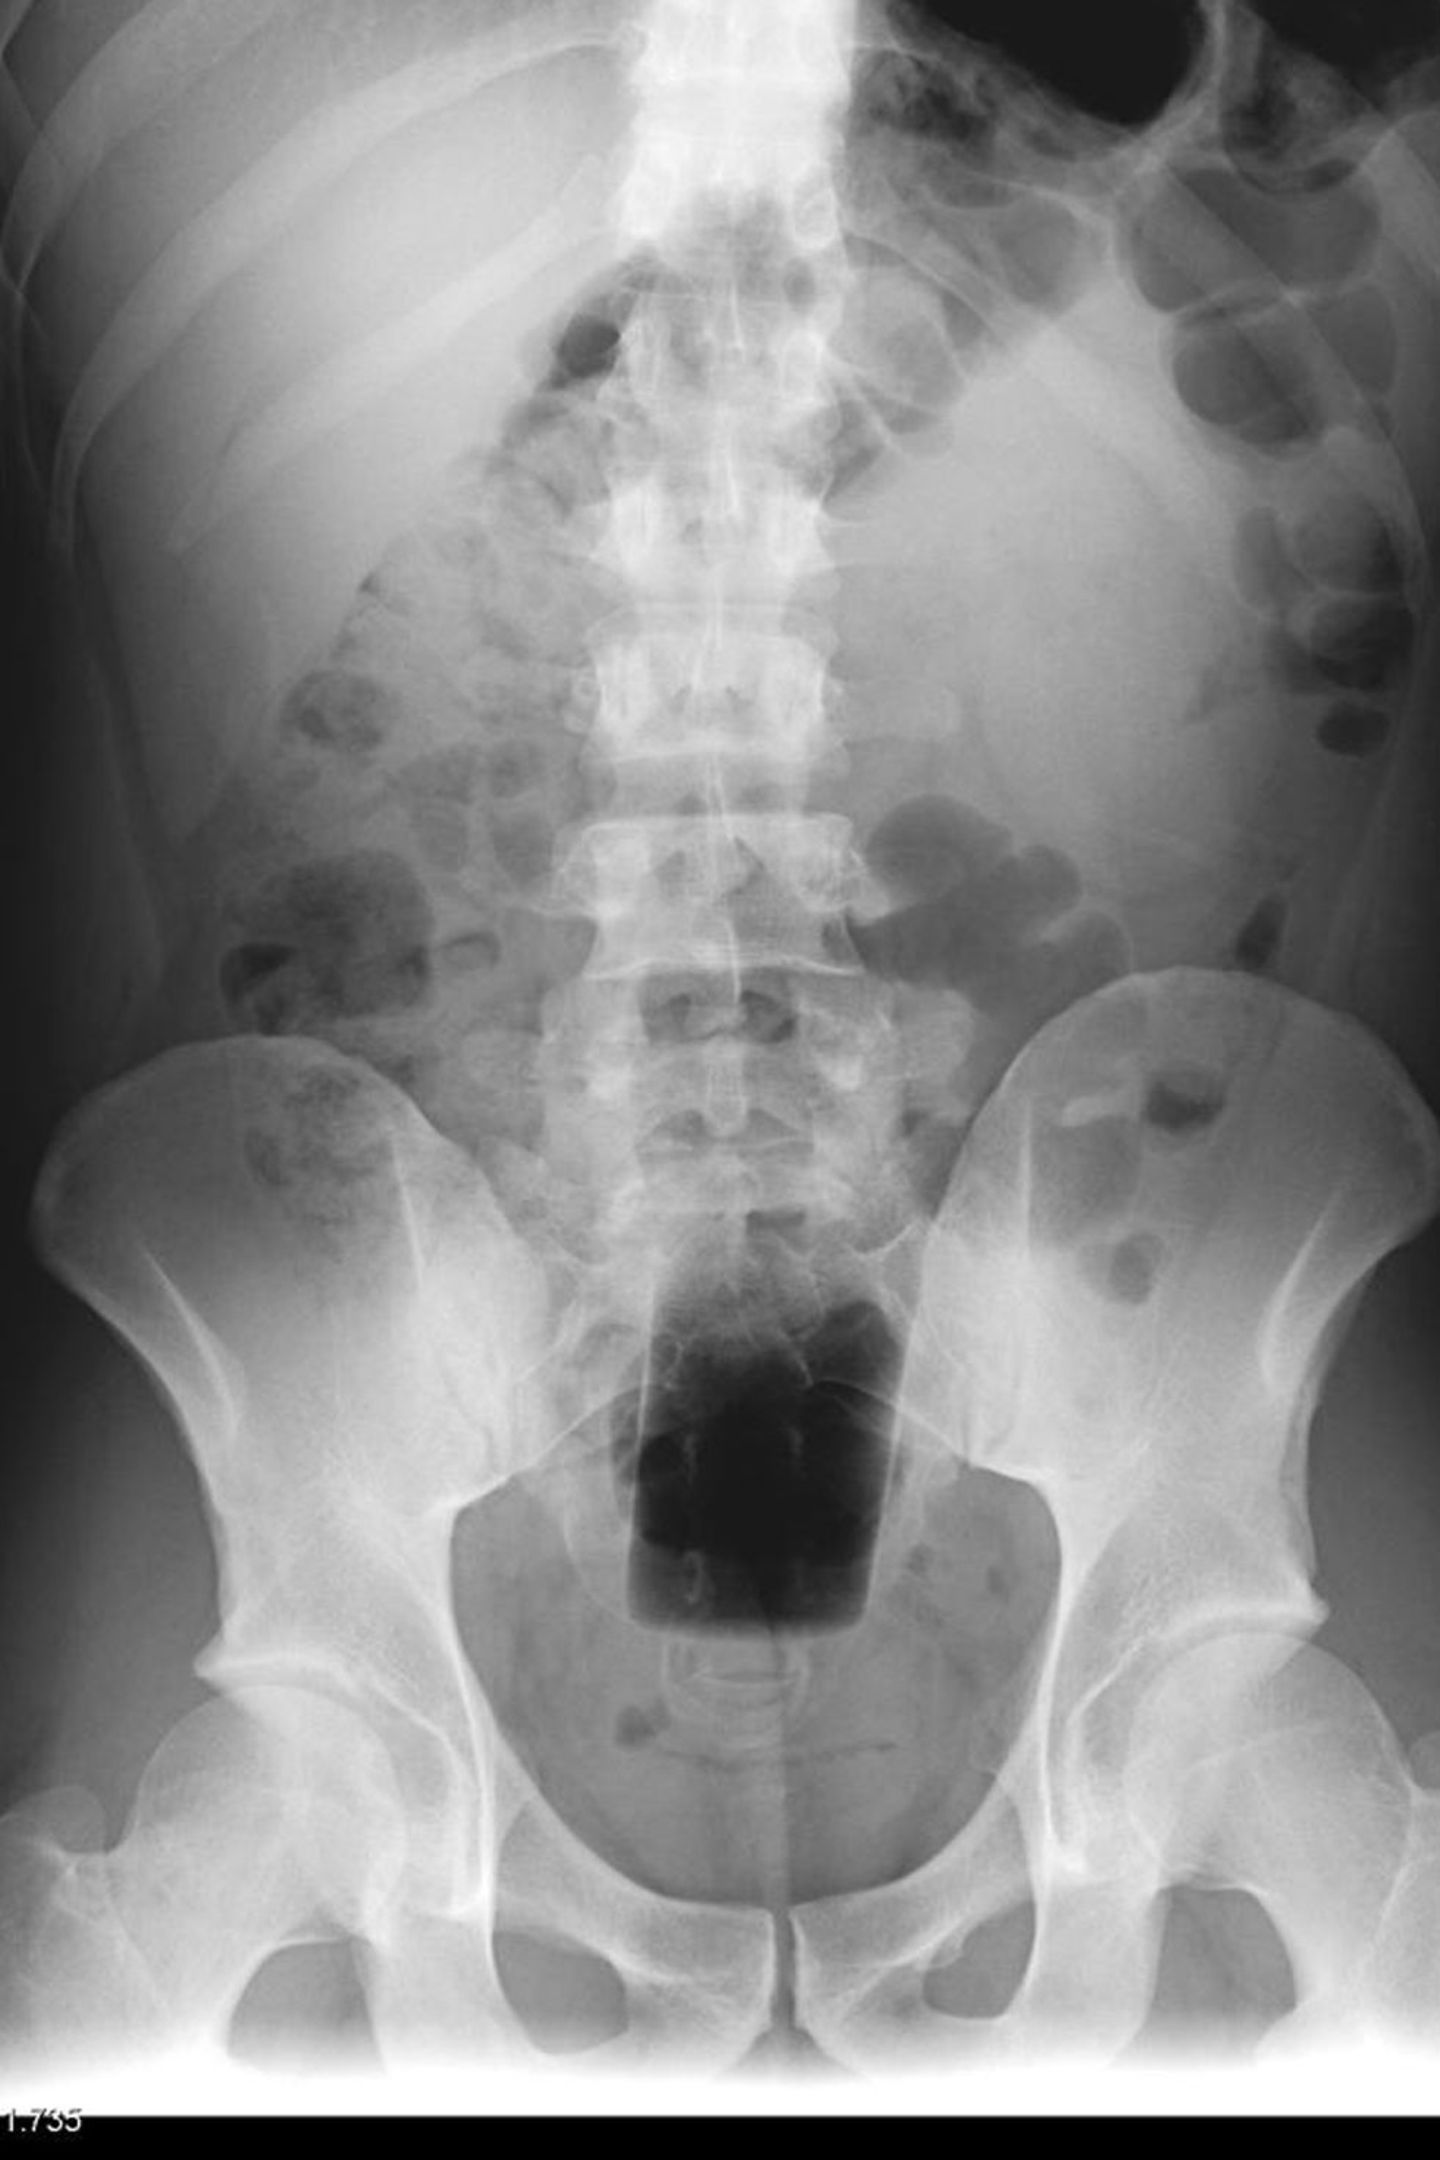

• Vom Dildo bis zur Orange: Was Ärzte auf Röntgenbildern entdecken

Hier ist der Boden einer Flasche erkennbar.